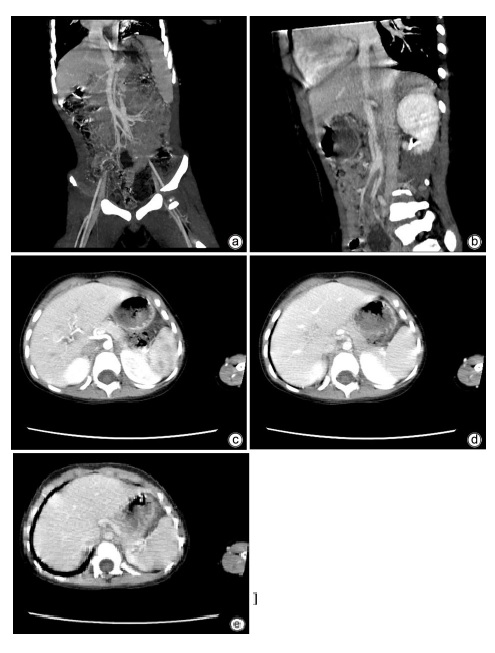

Transcatheter closure of rare type Ⅱ Abernethy malformation with pulmonary hypertension in children: A case report

Heng ZHANG, Bin JIANG, Zhicheng FANG, Zhongji MENG, Enfu DU

2023, 39(11): 2663-2667. DOI: 10.3969/j.issn.1001-5256.2023.11.022

Abstract(978) HTML (281) PDF (1074KB)(76)

Abstract:

Abernethy malformation, also known as congenital portosystemic shunts, is rare in clinical practice, with less than 300 cases reported in the global literature up to 2019. The disease can have serious complications such as pulmonary hypertension, liver tumor, and liver failure and tends to have an extremely poor prognosis, and early diagnosis and active and effective treatment can reduce and delay the onset of complications. In this case, portography combined with balloon occlusion helped to display the underdeveloped slender portal vein with dysplasia, so that the child who was formerly misdiagnosed with type Ⅰ Abernethy malformation was diagnosed with type Ⅱ Abernethy malformation, and then the child was successfully treated by transcatheter closure. This article gives a detailed report of this case.